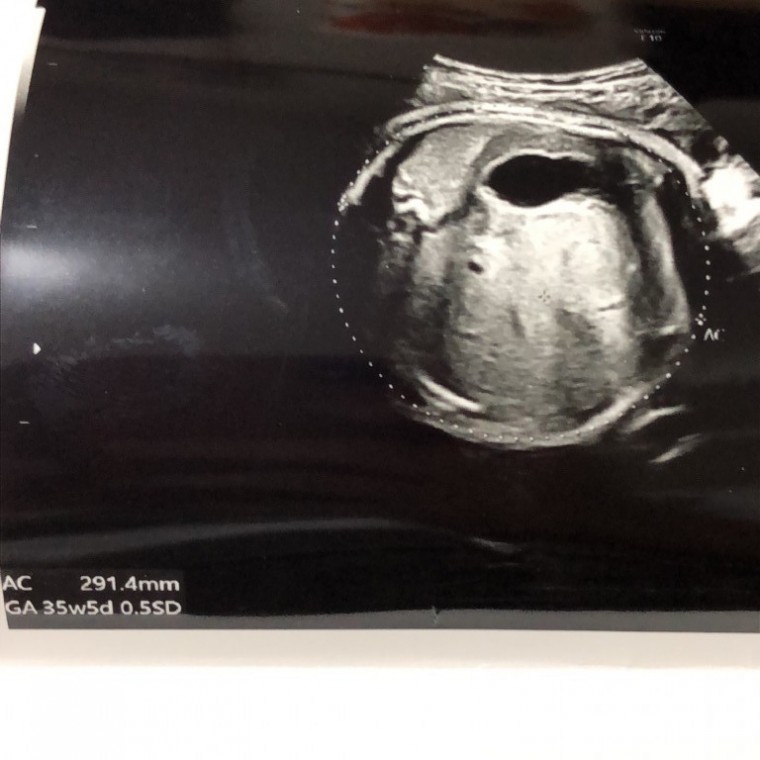

妊娠9ヶ月の超音波写真

妊娠9ヶ月(34週4日)撮影日:2018年9月12日